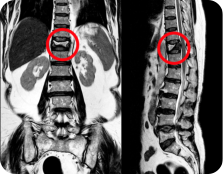

Herniated disks occur when part of the nucleus, the gel at the center of the disk, pushes back into the spinal canal. The injury to the disk can cause neck or low back pain. In some cases, it can also compress the nerves, causing pain, numbness and/or weakness in the arms or legs.